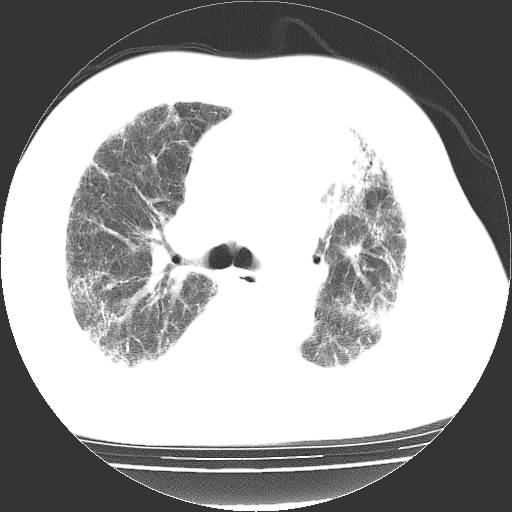

男,68岁,咳嗽、胸闷、发烧三天,查体:双肺散在湿罗音。

首先考虑特发型肺间质纤维化;两侧少量胸腔积液。

依据:1、两肺广泛条索状、网格状、蜂窝状改变。

根据3天的病史考虑 肺部感染,间质肺炎可能性大,网格及蜂窝影提示病灶时间较长结合肺纹混乱支持慢支炎,肺间质纤维化,肺心病,双侧胸腔积液。抗炎治疗复查

鉴别诊断:肺结核:病灶呈多形性改变,往往纤维化较多的病例,经常会有空洞;本例不大符合。

慢性支气管炎伴感染:临床病史不大支持,而且往往肺气肿较明显,本例不大明显。

双肺多发条索状、网格状及小灶状密度增高影。考虑慢支合并感染.间质纤维化,双侧少量胸腔积液

两肺广泛条索状、网格状、蜂窝状改变。肺间质纤维化,肺心病,双侧胸腔积液